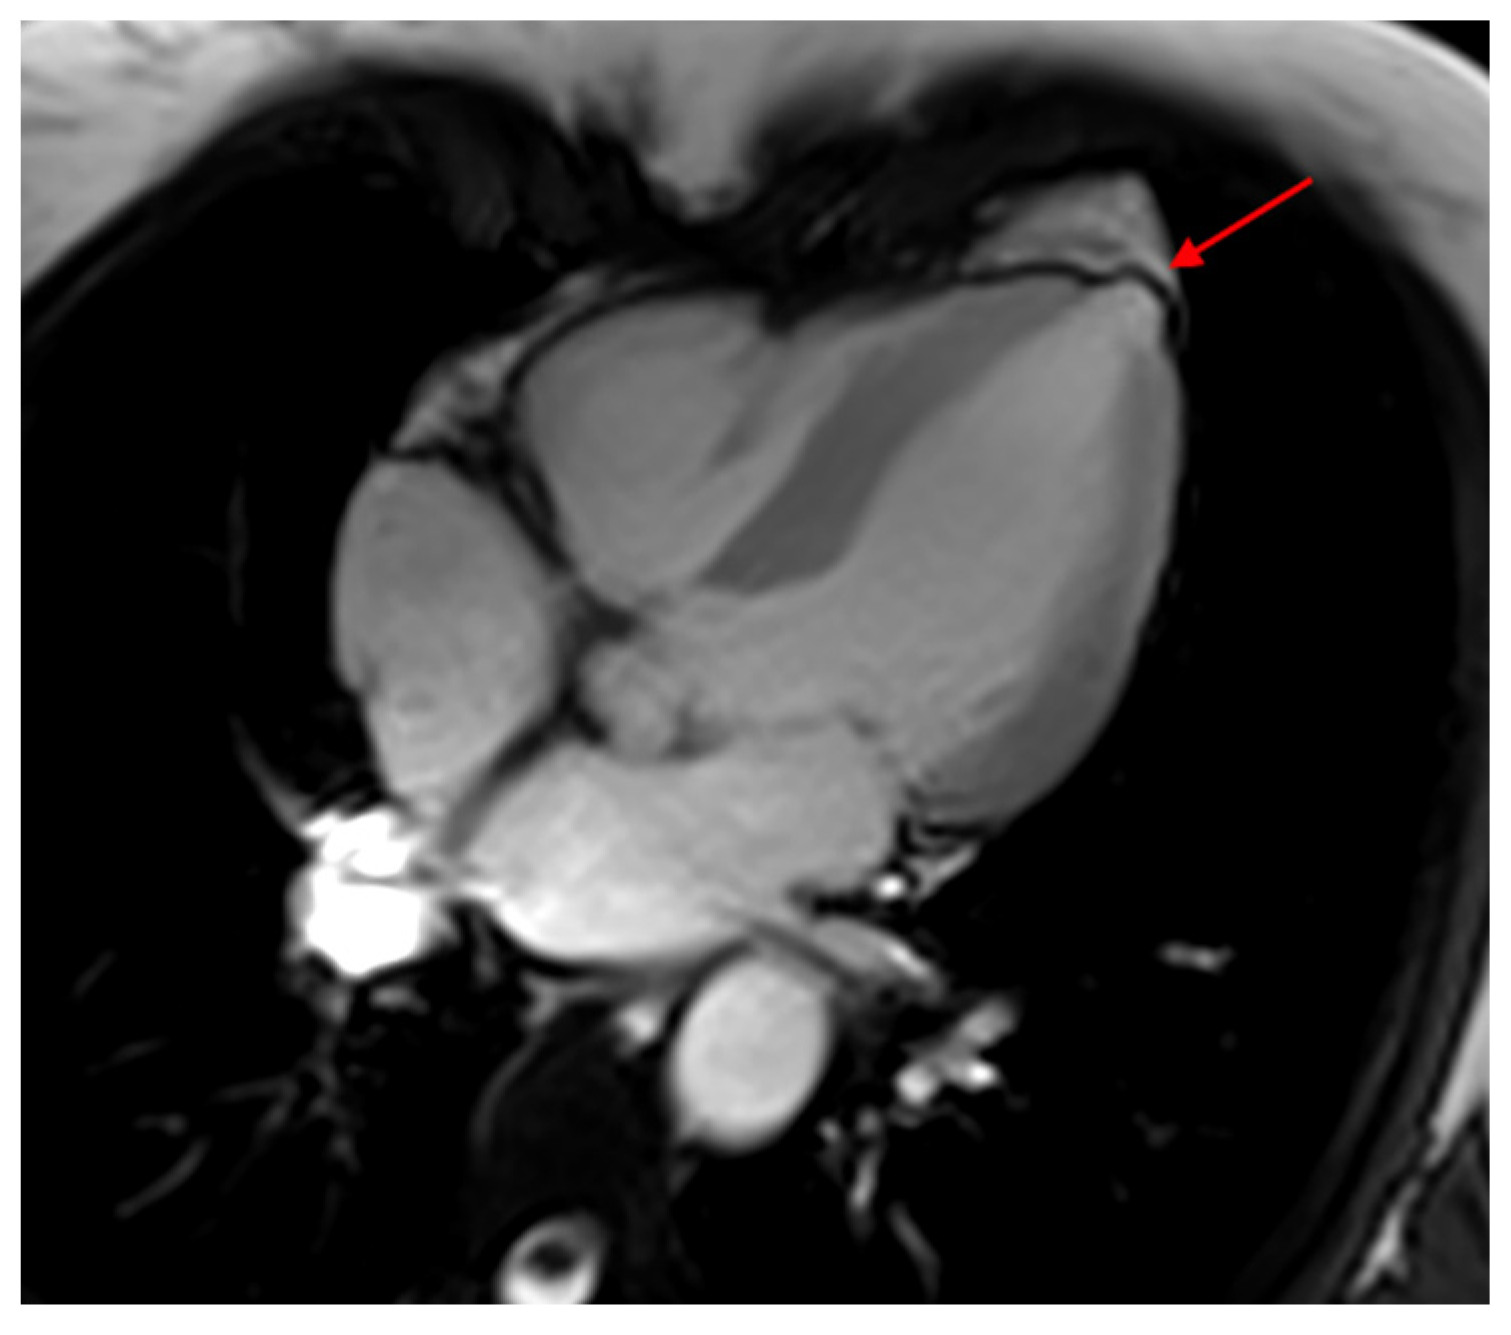

5. Cardiovascular Magnetic Resonance